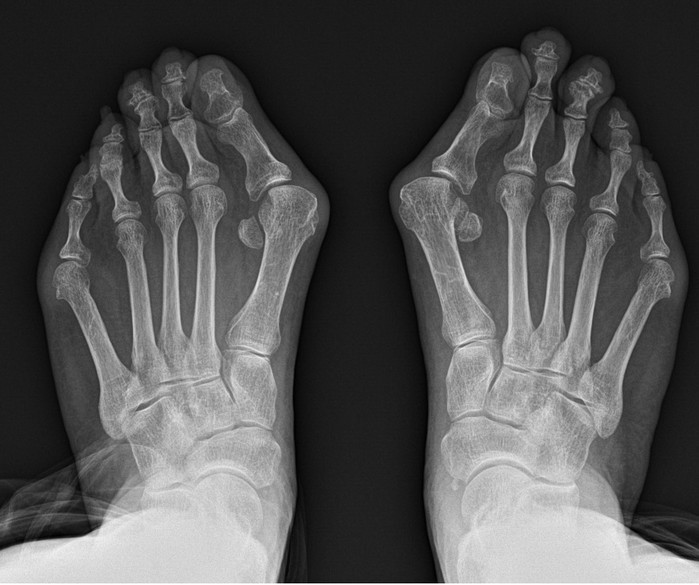

그 대표적인 예로 무지외반증을 꼽을 수 있다. 무지외반증 이란 엄지발가락이 새끼발가락 방향으로 휘며 엄지발가락이 시작되는 관절의 뼈가 돌출되는 질환이다.

무지외반증을 포함한 족부 질환 치료에 오랜 기간 매진해온 연세건우병원 박의현 병원장(정형외과 전문의)은 “무지외반증은 필연적으로 보행의 불균형을 유발한다. 정상인은 보행 시 엄지발가락에 체중의 약 60%가 실리지만 무지외반증 환자는 엄지발가락이 휘어져 있어서 그 반대로 발의 중지나 약지에 몸무게가 쏠려 정상적인 보행이 불가능해진다”고 설명한다.

그래서 무지외반증은 되도록 빨리 치료하면 좋지만 실제로 보행에 큰 지장이 오기 전까지는 방치하는 경우가 대다수다. 오랜기간 방치하게 되면 수술이 필요하게 되는데, 발은 여러 뼈가 얽혀있는 생각보다 복잡한 부위다. 그래서 환자들은 과연 수술 후 발 모양이 정상으로 돌아올지 그리고 통증은 심하지 않은지 걱정하게 된다.

박 병원장은 돌출 부 내측 한 부위 절개를 통해 교정과정의 부담을 최소화 했다. 변형이 심하거나 양측변형 이라도 엄지뼈를 안으로 밀어 넣어 소위 ‘칼발’로 불리는 교정이 가능하다. 교정이 변형되지 않도록 수술 후 일정기간 핀이나 나사로 고정하는 것으로 수술을 마친다. 수술 과정이 축소되면서 절개창도 기존과 달리 단일화 돼 통증 및 흉터 부담도 최소침습술 만큼 경감됐다.

연세건우병원에서 밝히 지난 6년간 중증 및 양측 무지외반증 환자의 장기 추시 결과에 따르면 사고·부상 등 외상 요인을 모두 포함해도 재발률이 0.5% 미만이다. 또한 고식적인 무지외반증 수술은 통증 점수(VAS)가 7~8점이지만, 단일절개 복합교정술은 통증 점수가 2~3점에 불과하다.